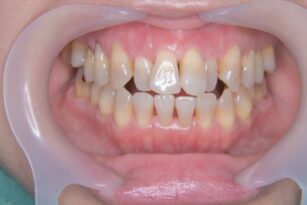

歯並びが気になる 20代 男性 部分矯正

下の歯並びが気になる 30代 男性 部分矯正